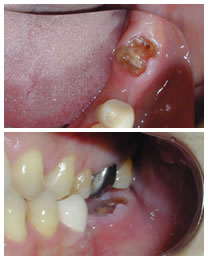

治療前

インプラント治療前左側下顎7番エクトリュージョンさせて、骨を新生させた上でインプラント植立した症例

初診時下顎口腔内写真と同左側側方面観